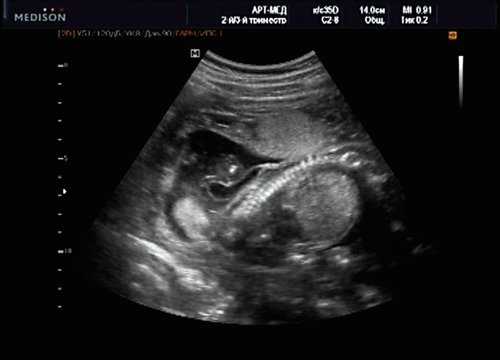

При эхокардиографии изучались четырехкамерный срез сердца плода (рис. 1) и срез через три сосуда (рис. 2). УЗИ проводилось трансабдоминальным датчиком, лишь при необходимости (затрудненная визуализация) использовался внутриполостной датчик. Четырехкамерный срез сердца плода при ультразвуковом сканировании трансабдоминальным датчиком визуализировался в 85% случаев, срез через сосуды - в 73%, при использовании трансвагинального датчика эти цифры существенно возрастали до 100 и 91% соответственно. Оптимизация пренатальной диагностики ВПС может быть достигнута путем строгого соблюдения основных методических правил. При оценке четырехкамерного среза плода необходимо оценить нормальное расположение сердца плода, исключив его эктопию (рис. 3), положение оси сердца плода, что не представляет никаких трудностей, нормальные пропорции и размеры камер сердца, движение створок атриовентрикулярных клапанов должно быть свободным, септальная створка трикуспидального клапана должна располагаться ближе к верхушке сердца (рис. 4). При оценке среза через три сосуда необходимо оценить взаиморасположение сосудов и их диаметр.